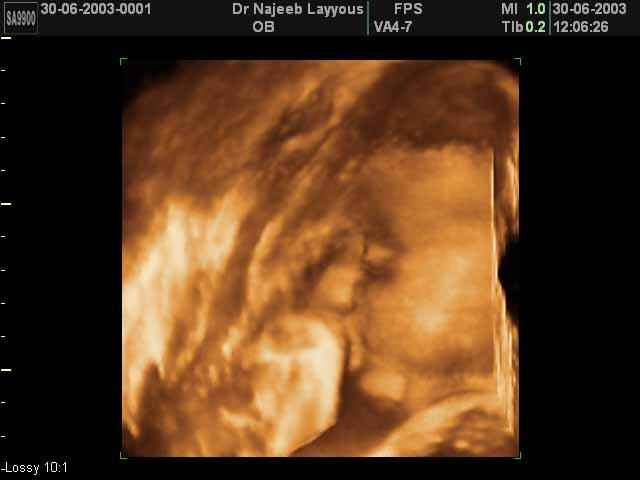

- صور جانبية لرأس الجنين

صور جانبية لرأس الجنين بجهاز الالتراساوند ثلاثي الأبعاد | الدكتور نجيب ليوس